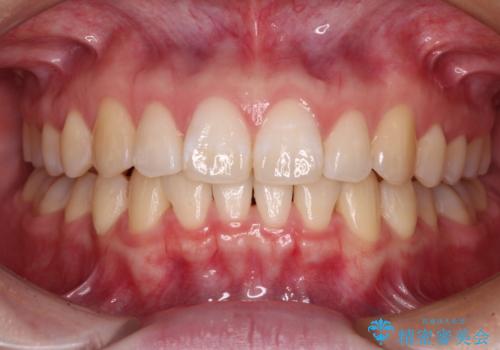

矯正歯科治療 → 叢生(でこぼこ・八重歯)

『目立たない装置で前歯のガタガタを治したい』インビザライン症例